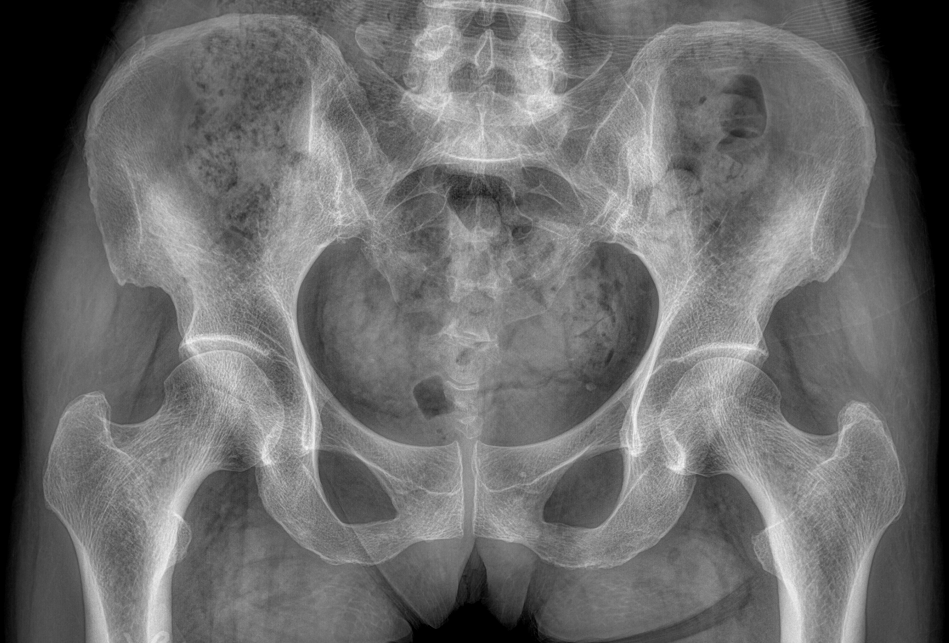

• 拍片

适用于全身各部位摄影

(常规摄影和特殊摄影)

临床图像